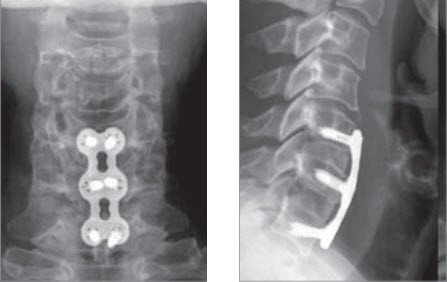

Da die entfernte Bandscheibe einen «Hohlraum» zurücklässt, wird dieser mit einem Platzhalter ausgefüllt. Dies kann mit eigenem Knochen (Beckenkamm) oder mit Fremdmaterial (sog. Cage) erfolgen. Damit erreicht man gleichzeitig eine Verblockung der Wirbelkörper, die mit einer Platte gesichert werden kann. Diese Versteifung beeinträchtigt die Gesamtbeweglichkeit der Halswirbelsäule kaum. Gelegentlich wird anstelle der Verblockung die Bandscheibe durch eine bewegliche Prothese ersetzt.